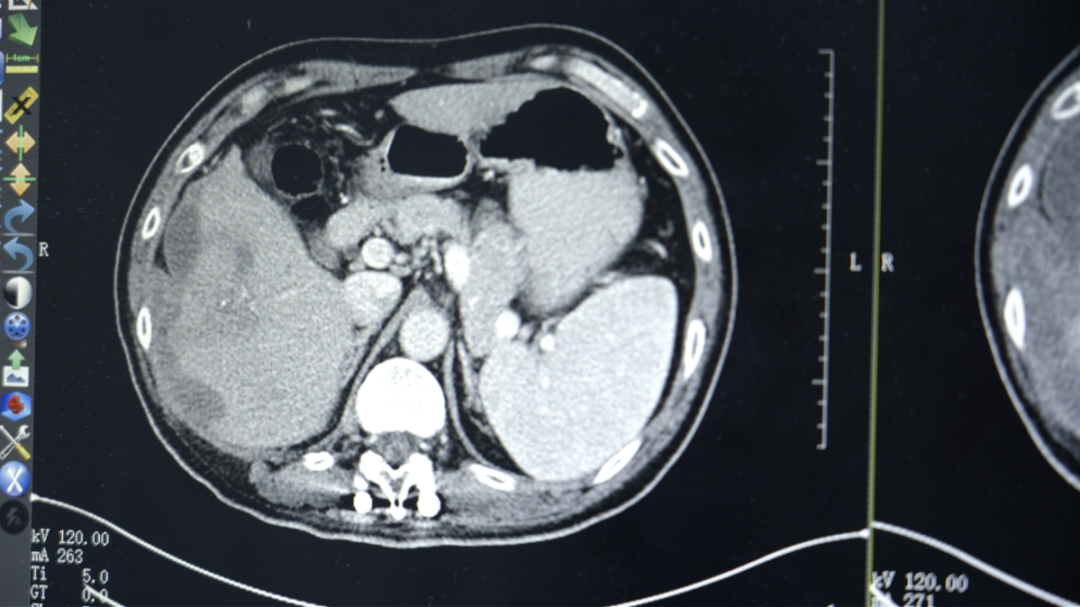

在当地医院,勇哥接受了一次介入灌注化疗栓塞术,但反应剧烈,“反复发烧,烧了足足半个月”。好不容易烧退了,复查结果却更令人绝望:肝脏病灶扩大到13.2厘米,肺转移瘤增多,肝门区、腹腔淋巴结密密麻麻。医生跟他说肿瘤扩散太广,无法手术,最多只剩“两个月时间”。

“吃了药,打了针,不怎么疼了,能吃饭能睡觉了。”几个疗程后,勇哥的生活质量明显改善。复查结果显示肿瘤得到控制,甲胎蛋白降至1.8万ng/ml。考虑到肝脏上病灶负荷太大,且紧靠周边,出血风险比较高,李红梅主任还是建议他进行肝动脉灌注化疗术(HAIC)。

第三次回院复查时,勇哥的甲胎蛋白已降至800多,CT显示肝癌及肝内多发转移瘤、双肺转移瘤及大网膜转移瘤都较前缩小,无新发病灶,病情评价为稳定(SD)。“这次做介入治疗时,医生告诉我肝上肿瘤基本没有活性了。”勇哥的声音中带着久违的轻松。